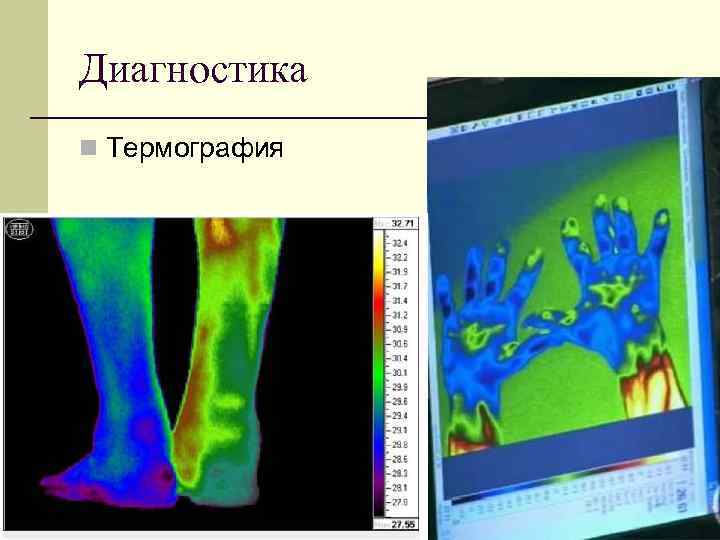

Диагностика n Термография